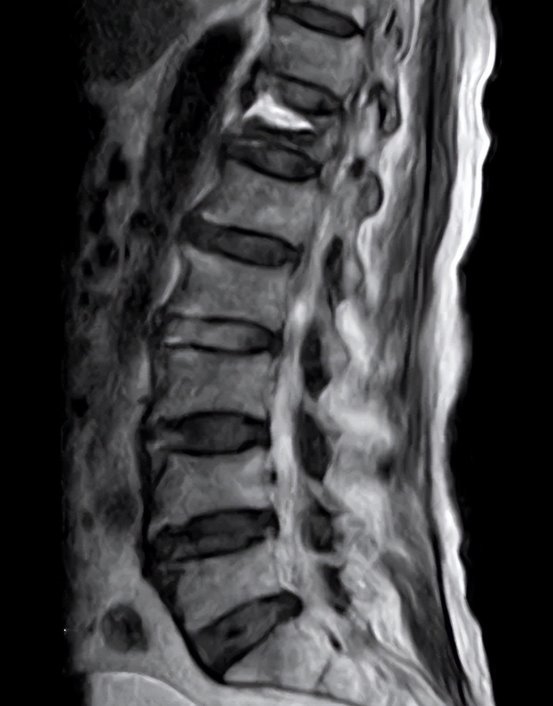

经过我院脊柱外科团队详细且全面的检查,李奶奶被确诊为胸椎 Kummell 病。面对这一复杂病症,考虑到李奶奶年事已高,传统手术方式可能带来诸多风险,如长时间卧床易引发泌尿道感染、褥疮等并发症。脊柱外科团队经过审慎讨论,最终决定采用 PKP 微创手术。

那么,究竟什么是 Kummell 病呢?Kummell 病,又称库曼氏病或椎体缺血性坏死,是一种骨质疏松性椎体压缩骨折的迟发性并发症。这一病症最早由德国医生 Hermann Kummell 提出。它的核心特征十分明显:患者在经历轻微外伤后,会在数周至数月内出现腰背部胀痛不适,随着时间的推移,疼痛不仅不会缓解,反而会逐渐加重,发展为持续性腰背痛,同时伴随椎体塌陷、后凸畸形,严重时甚至会导致神经功能障碍,严重影响患者的生活质量。